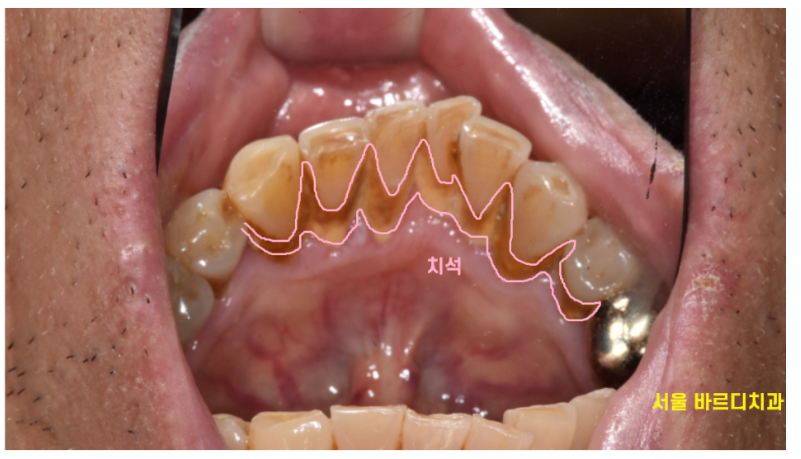

230704 이 두꺼운 치석들 그냥 두고 볼 수 없겠죠?

스케일링을 하면 치아가 깎여서 공간이 생기는 것이 아니라,

원래부터 있던 치석이 제거되면서

본래의 치아 형태가 드러나는 것입니다.

원래 치아가 벌어져있었는데...

치석이 그 공간을 메꿨던 것일뿐..

사실은 잇몸이 내려가면서

그 공간이 치석으로 채워졌던것이랍니다.